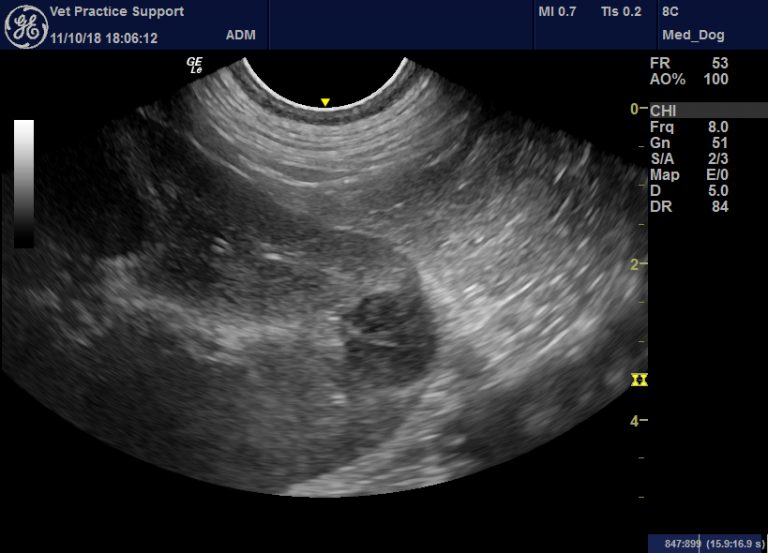

From www.vetpracticesupport.com

Persistent cutaneous flushing associated with presumed renal neoplasia Kidney Flush For Dogs Intravenous fluids are the main treatment for acute kidney failure. Common symptoms of kidney failure in dogs include increased thirst, lethargy, diarrhea, excessive urination, and dehydration. Kidney failure is an irreversible process that affects about 1 in 200 dogs of all ages and is far more common as dogs age. In dogs, chronic kidney disease is associated with aging, and. Kidney Flush For Dogs.